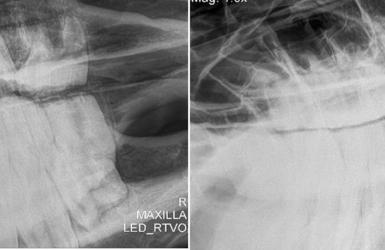

Der Zustand der Zähne der Urpferde kann in vielerlei Hinsicht als Vorbild für die Zielsetzung der hier praktizierten Pferdezahnbehandlung dienen.

Die folgenden beiden Bilder stammen aus dem Pferdemuseum Münster. Dort wird anhand der urzeitlichen Schädel die Evolution des Pferdes dargestellt.

Die Zähne der Urpferde (erstes und zweites Bild oben) waren durch die natürliche Nahrungsaufnahme auch ohne Pferdezahnarzt ausbalanciert und frei von scharfen Kanten und Haken.